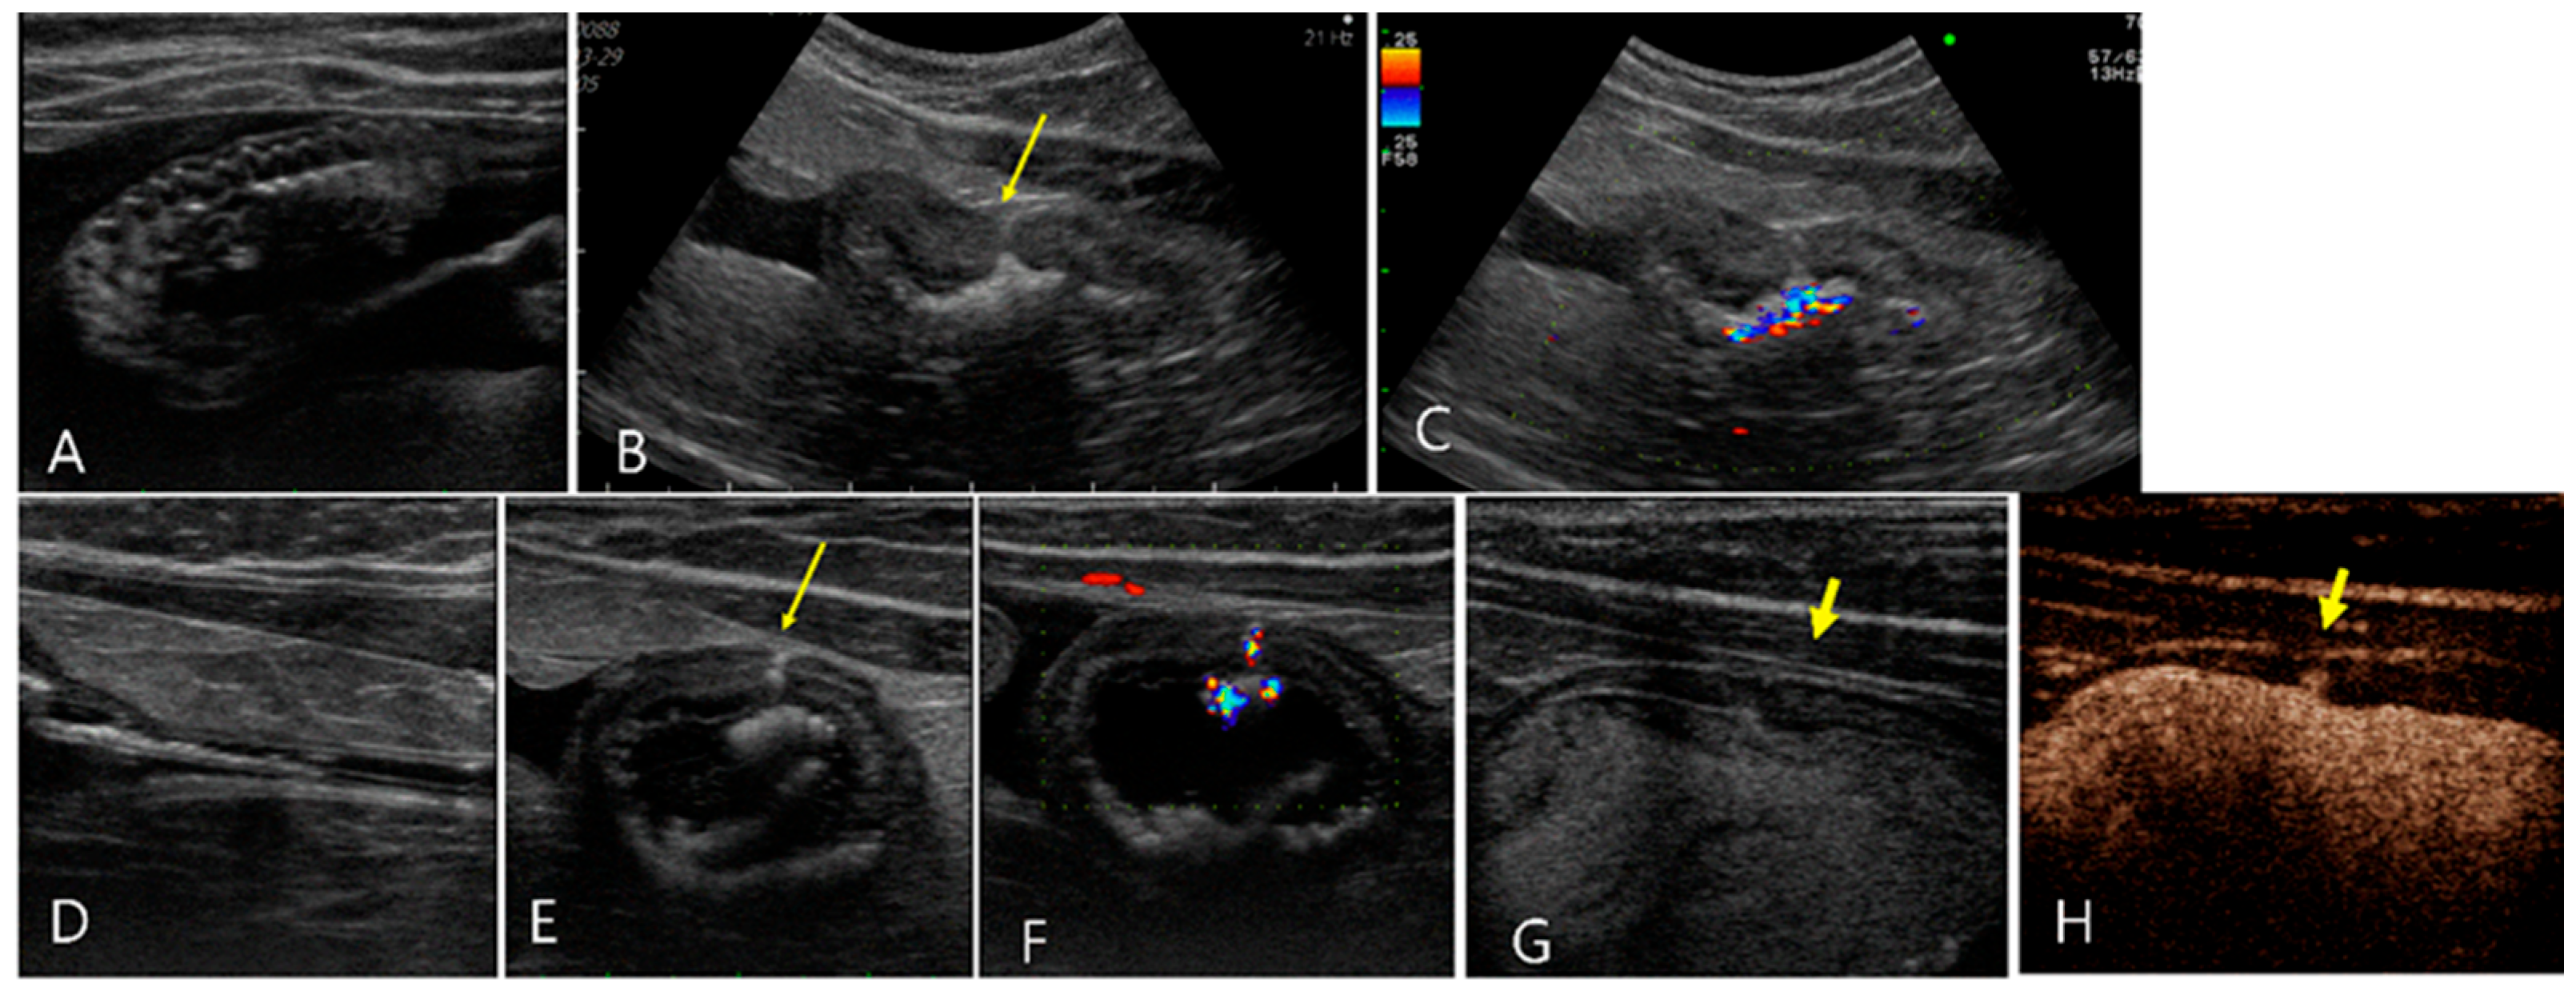

2.1. Case 1

2.2. Case 2

2.3. Case 3

2.4. Case 4

2.5. Case 5

2.6. Case 6